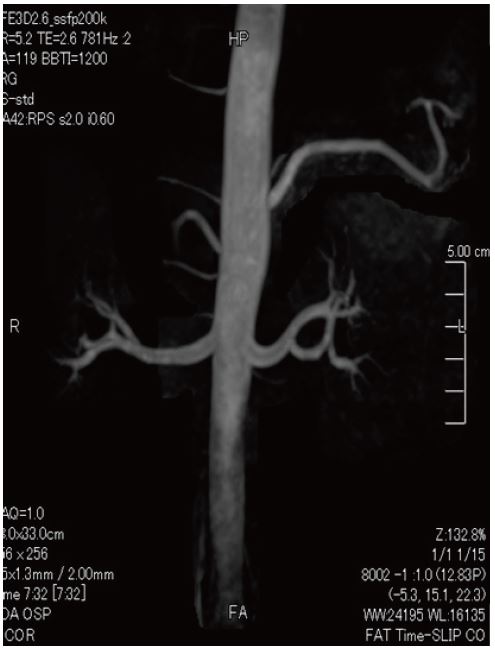

Ангіо-МРТ з використанням методу Time-SLIP

46-річна людина, гіпертонік, ангіо-МРТ з використанням методу Time-SLIP

Метод Time-SLIP

Техніка з використанням парамагнитного контрасту